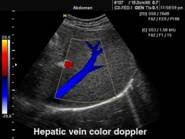

В Центре современных медицинских технологий «АКВА МЕД МАРИН» проводится УЗИ-диагностика на новейших ультразвуковых диагностических сканерах Экспертного класса SonoScape S40Exp и Премиум класса Toshiba SSA-780A, в том числе и УЗИ детям с применением специальных детских датчиков. Цветной допплер помогает точной диагностике патологии сосудов и сердца у взрослых и детей.

Компания SonoScape уделила особое внимание допплеровским режимам и является экспертом в своем классе, что позволяет с легкостью, но в то же время с уникальной точностью проводить исследования с постановкой наиболее точного диагноза.

Ультразвуковые исследования, доплеровское сканирование сосудов в Центре современных медицинских технологий «АКВА МЕД МАРИН» выполняется при помощи первого и единственного аппарата в Керчи SonoScape S40Exp (экспертного класса, который оснащен множеством новейших функций, многократно улучшающих качество и информативность УЗИ-исследования).